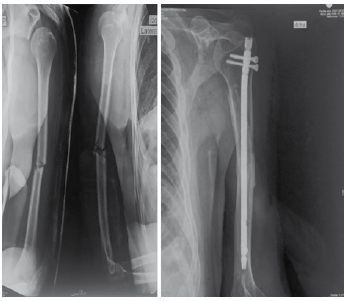

La técnica osteosíntesis indirecta a través del clavo endomedular para húmero UHN, con dos vías de inserción anterógrada y retrógrada; en ambos se determinó preoperatoriamente la longitud y diámetro del clavo. Técnica quirúrgica anterógrada: Se realiza abordaje lateral al acromion, disección de fibras del deltoides, se identifica tendón supraespinoso, incisión longitudinal del tendón, inserción de aguja de Kirschner y punzón iniciador hasta abrir cavidad medular, se introduce clavo previa reducción por maniobras externas del foco de fractura. Se procede a bloqueo distal a manos libres con control fluoroscópico y bloqueo proximal con guía de arco de inserción. Y reparación de músculo supraespinoso18. (Figura N° 1)

Figura N° 1. Radiografía con proyección anteroposterior y lateral donde se visualiza Fractura Humero diafisario izquierdo (imagen izquierda) Reducción indirecta mediante técnica de enclavado endomedular vía anterógrada. (imagen derecha)

Fuente: Propia